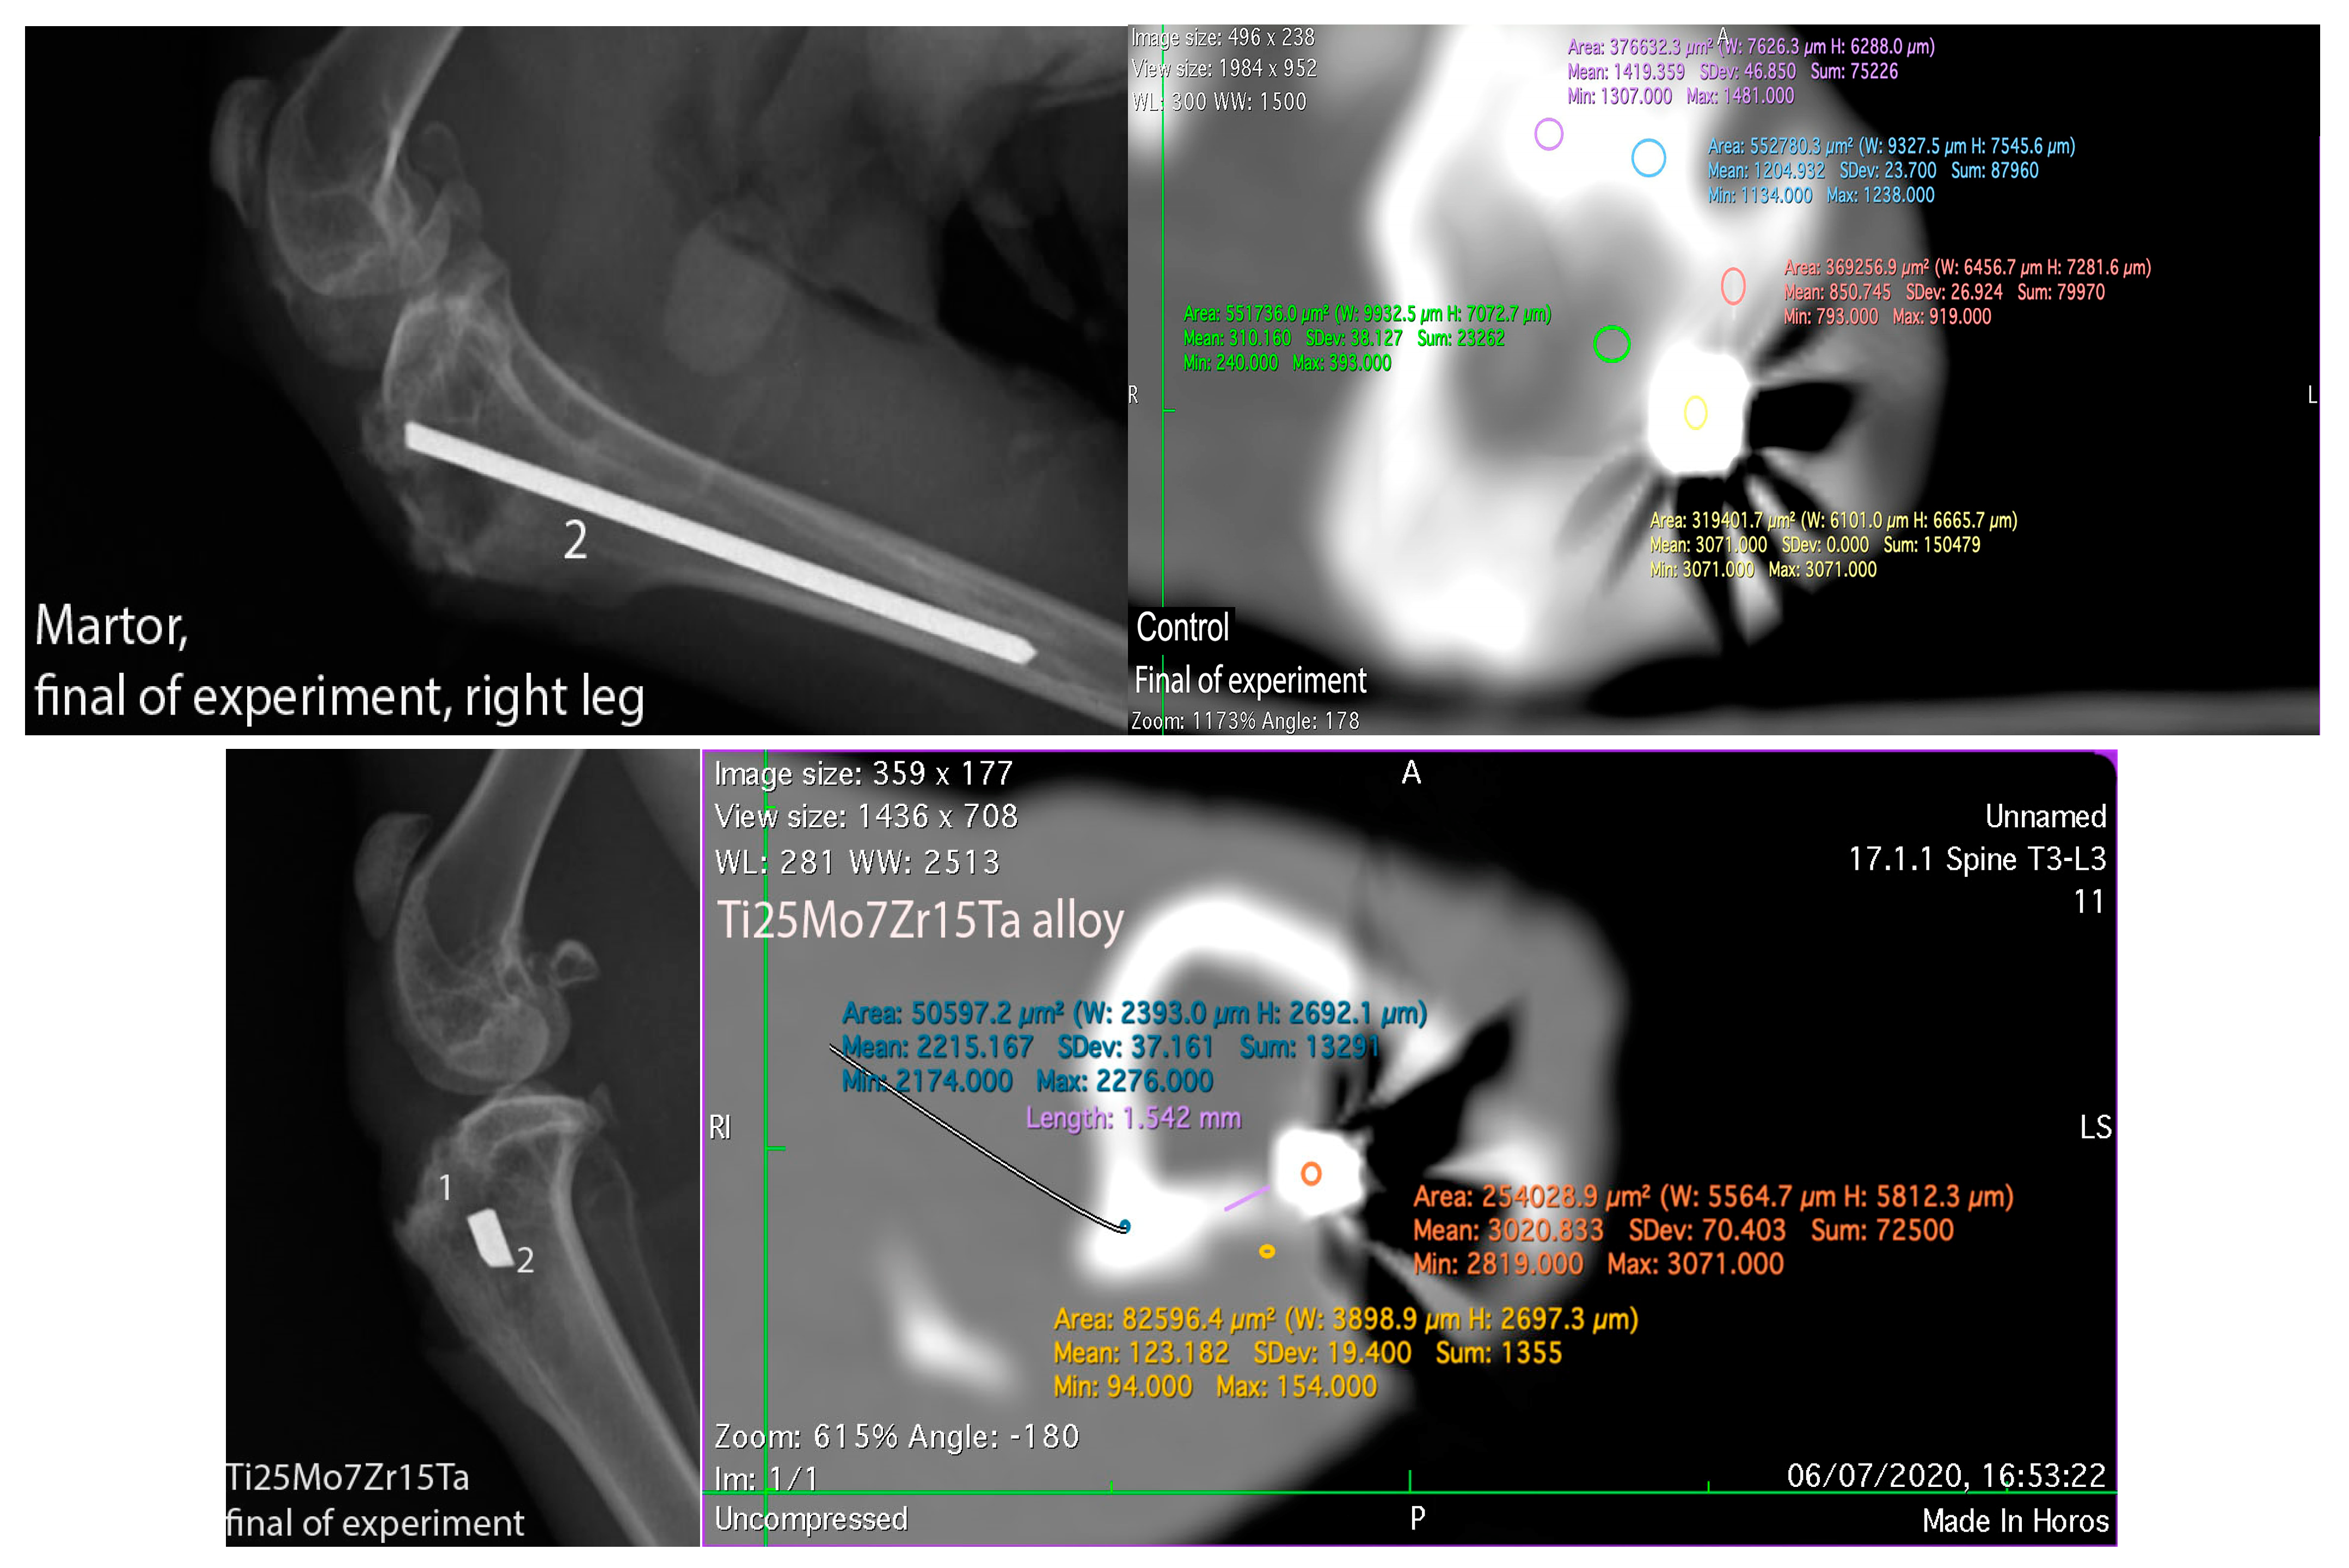

3.3. Interpretation of Results, Radiographs and Micrographs